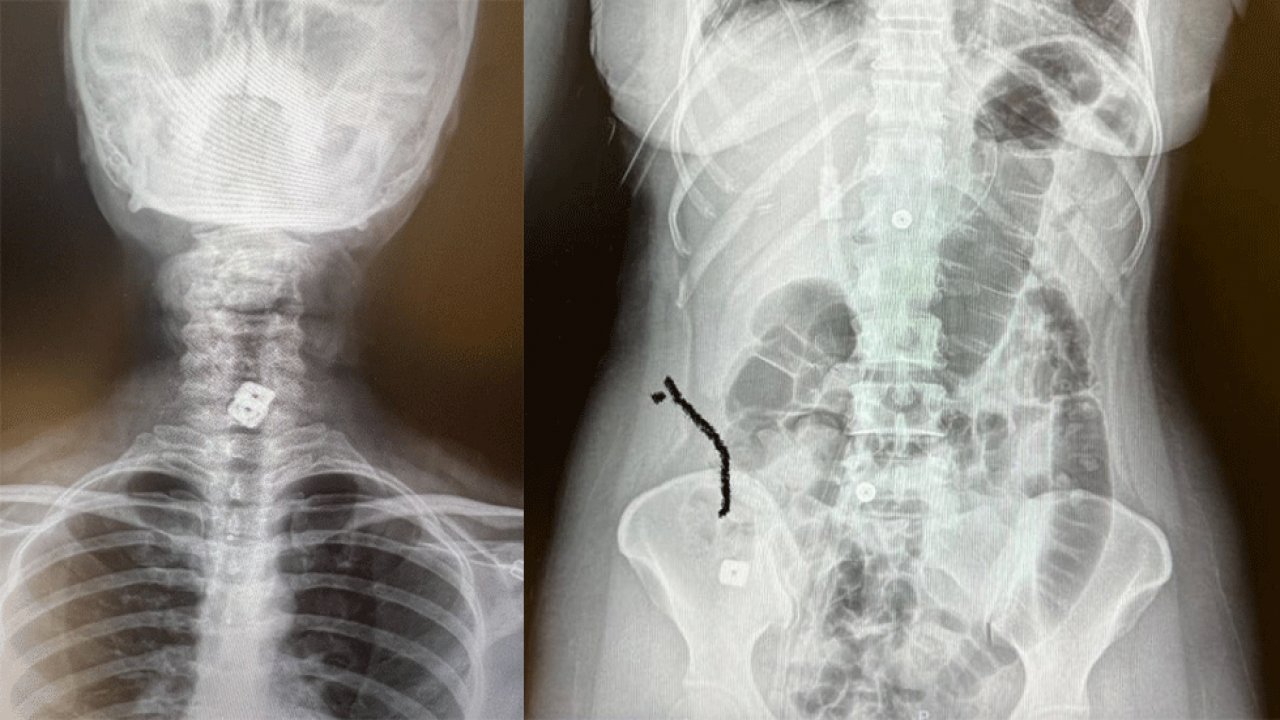

SAKO’da tıp tarihine geçen olay! Boyuna takılan disk yemek borusunu delip mideye indi!